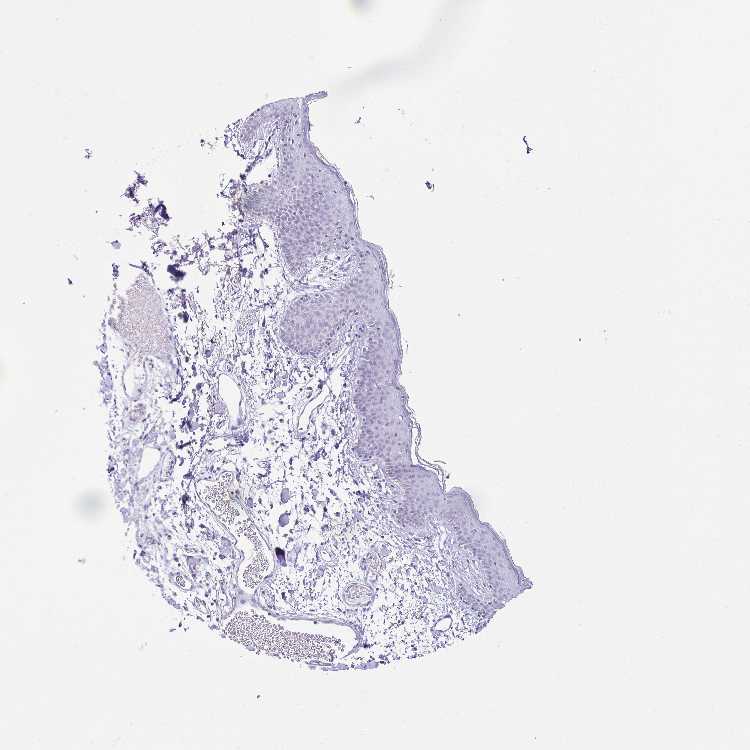

SKIN 1 - Antibody stainingi

Antibody staining in the annotated cell types in the current human tissue is reported as not detected, low, medium, or high, based on conventional immunohistochemistry profiling in selected tissues. This score is based on the combination of the staining intensity and fraction of stained cells.

Each image is clickable and will lead to virtual microscopy that enables deeper exploration of all samples and also displays staining intensity scores, fraction scores and subcellular localization as well as patient and tissue information for each sample.

Antibody HPA053339Antibody HPA055040

Langerhans Not detectedNot detected

Fibroblasts Not detectedNot detected

Keratinocytes Not detectedNot detected

Melanocytes Not detectedNot detected